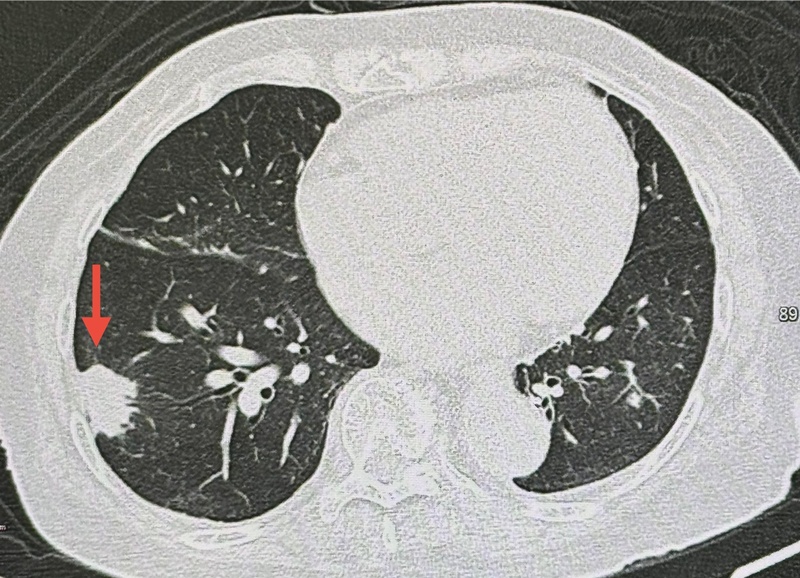

ผู้ป่วยรายนี้ มาตรวจร่างกายประจำปี ตรวจร่างกาย ไม่มีไข้ ฟังปอดปกติ เอกซเรย์ปอด มีเงาผิดปกติปอดข้างขวาด้านบนจากเคยป่วยเป็นวัณโรค และมีก้อนขนาด 1.9 x 1.9 เซนติเมตรที่ปอดข้างขวาด้านล่าง (ดูรูป) ก้อนนี้เป็นก้อนใหม่เพิ่งพบครั้งแรก ปีที่แล้วไม่มีก้อน ทำคอมพิวเตอร์ปอด พบก้อนขนาด 3.0 × 2.4 × 2.0 เซนติเมตรที่ปอดข้างขวาด้านล่าง ตรวจเลือด ค่ามะเร็งทุกตัวปกติ

เมื่อเจาะก้อนด้วยเข็ม ส่งชิ้นเนื้อตรวจพยาธิวิทยา พบปอดอักเสบจากเชื้อราคริปโตค็อกคัส ตรวจเลือดหาคริปโตค็อกคัสแอนติเจนให้ผลบวก titer 1 : 20 ทำคอมพิวเตอร์สมอง และเจาะน้ำไขสันหลังปกติ ไม่พบเชื้อราคริปโตค็อกคัสกระจายเข้าเยื่อหุ้มสมอง

วินิจฉัย : ปอดอักเสบจากติดเชื้อราคริปโตค็อกคัส